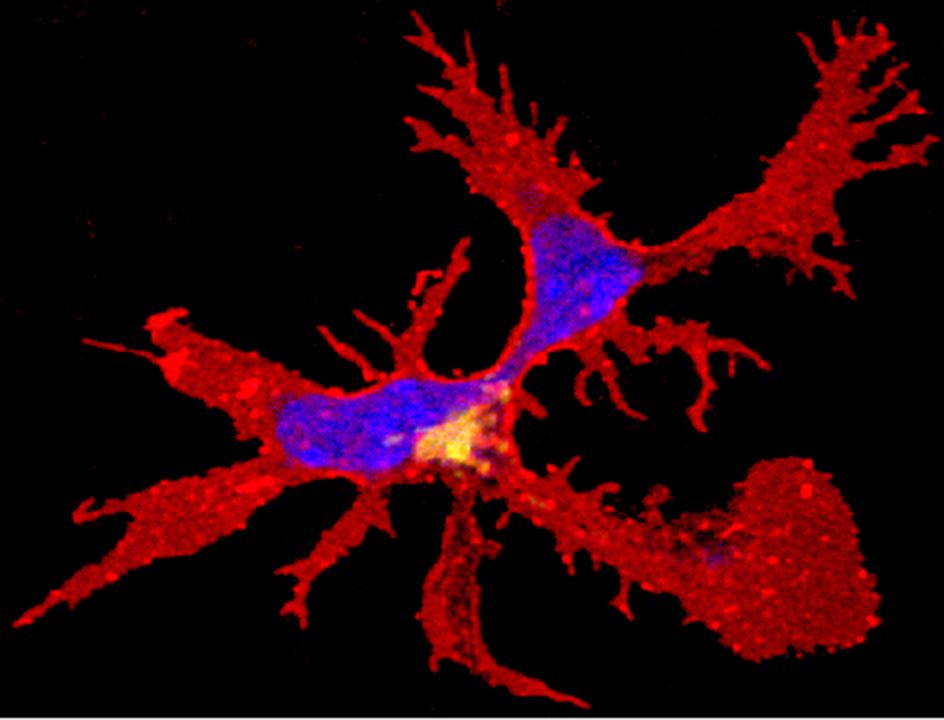

Dendritic cell. Credit: WEHI

WEHI researchers have made a surprise discovery about how immune ‘sentinel’ cells are maintained, which could have implications for drugs in development for treating cancer.